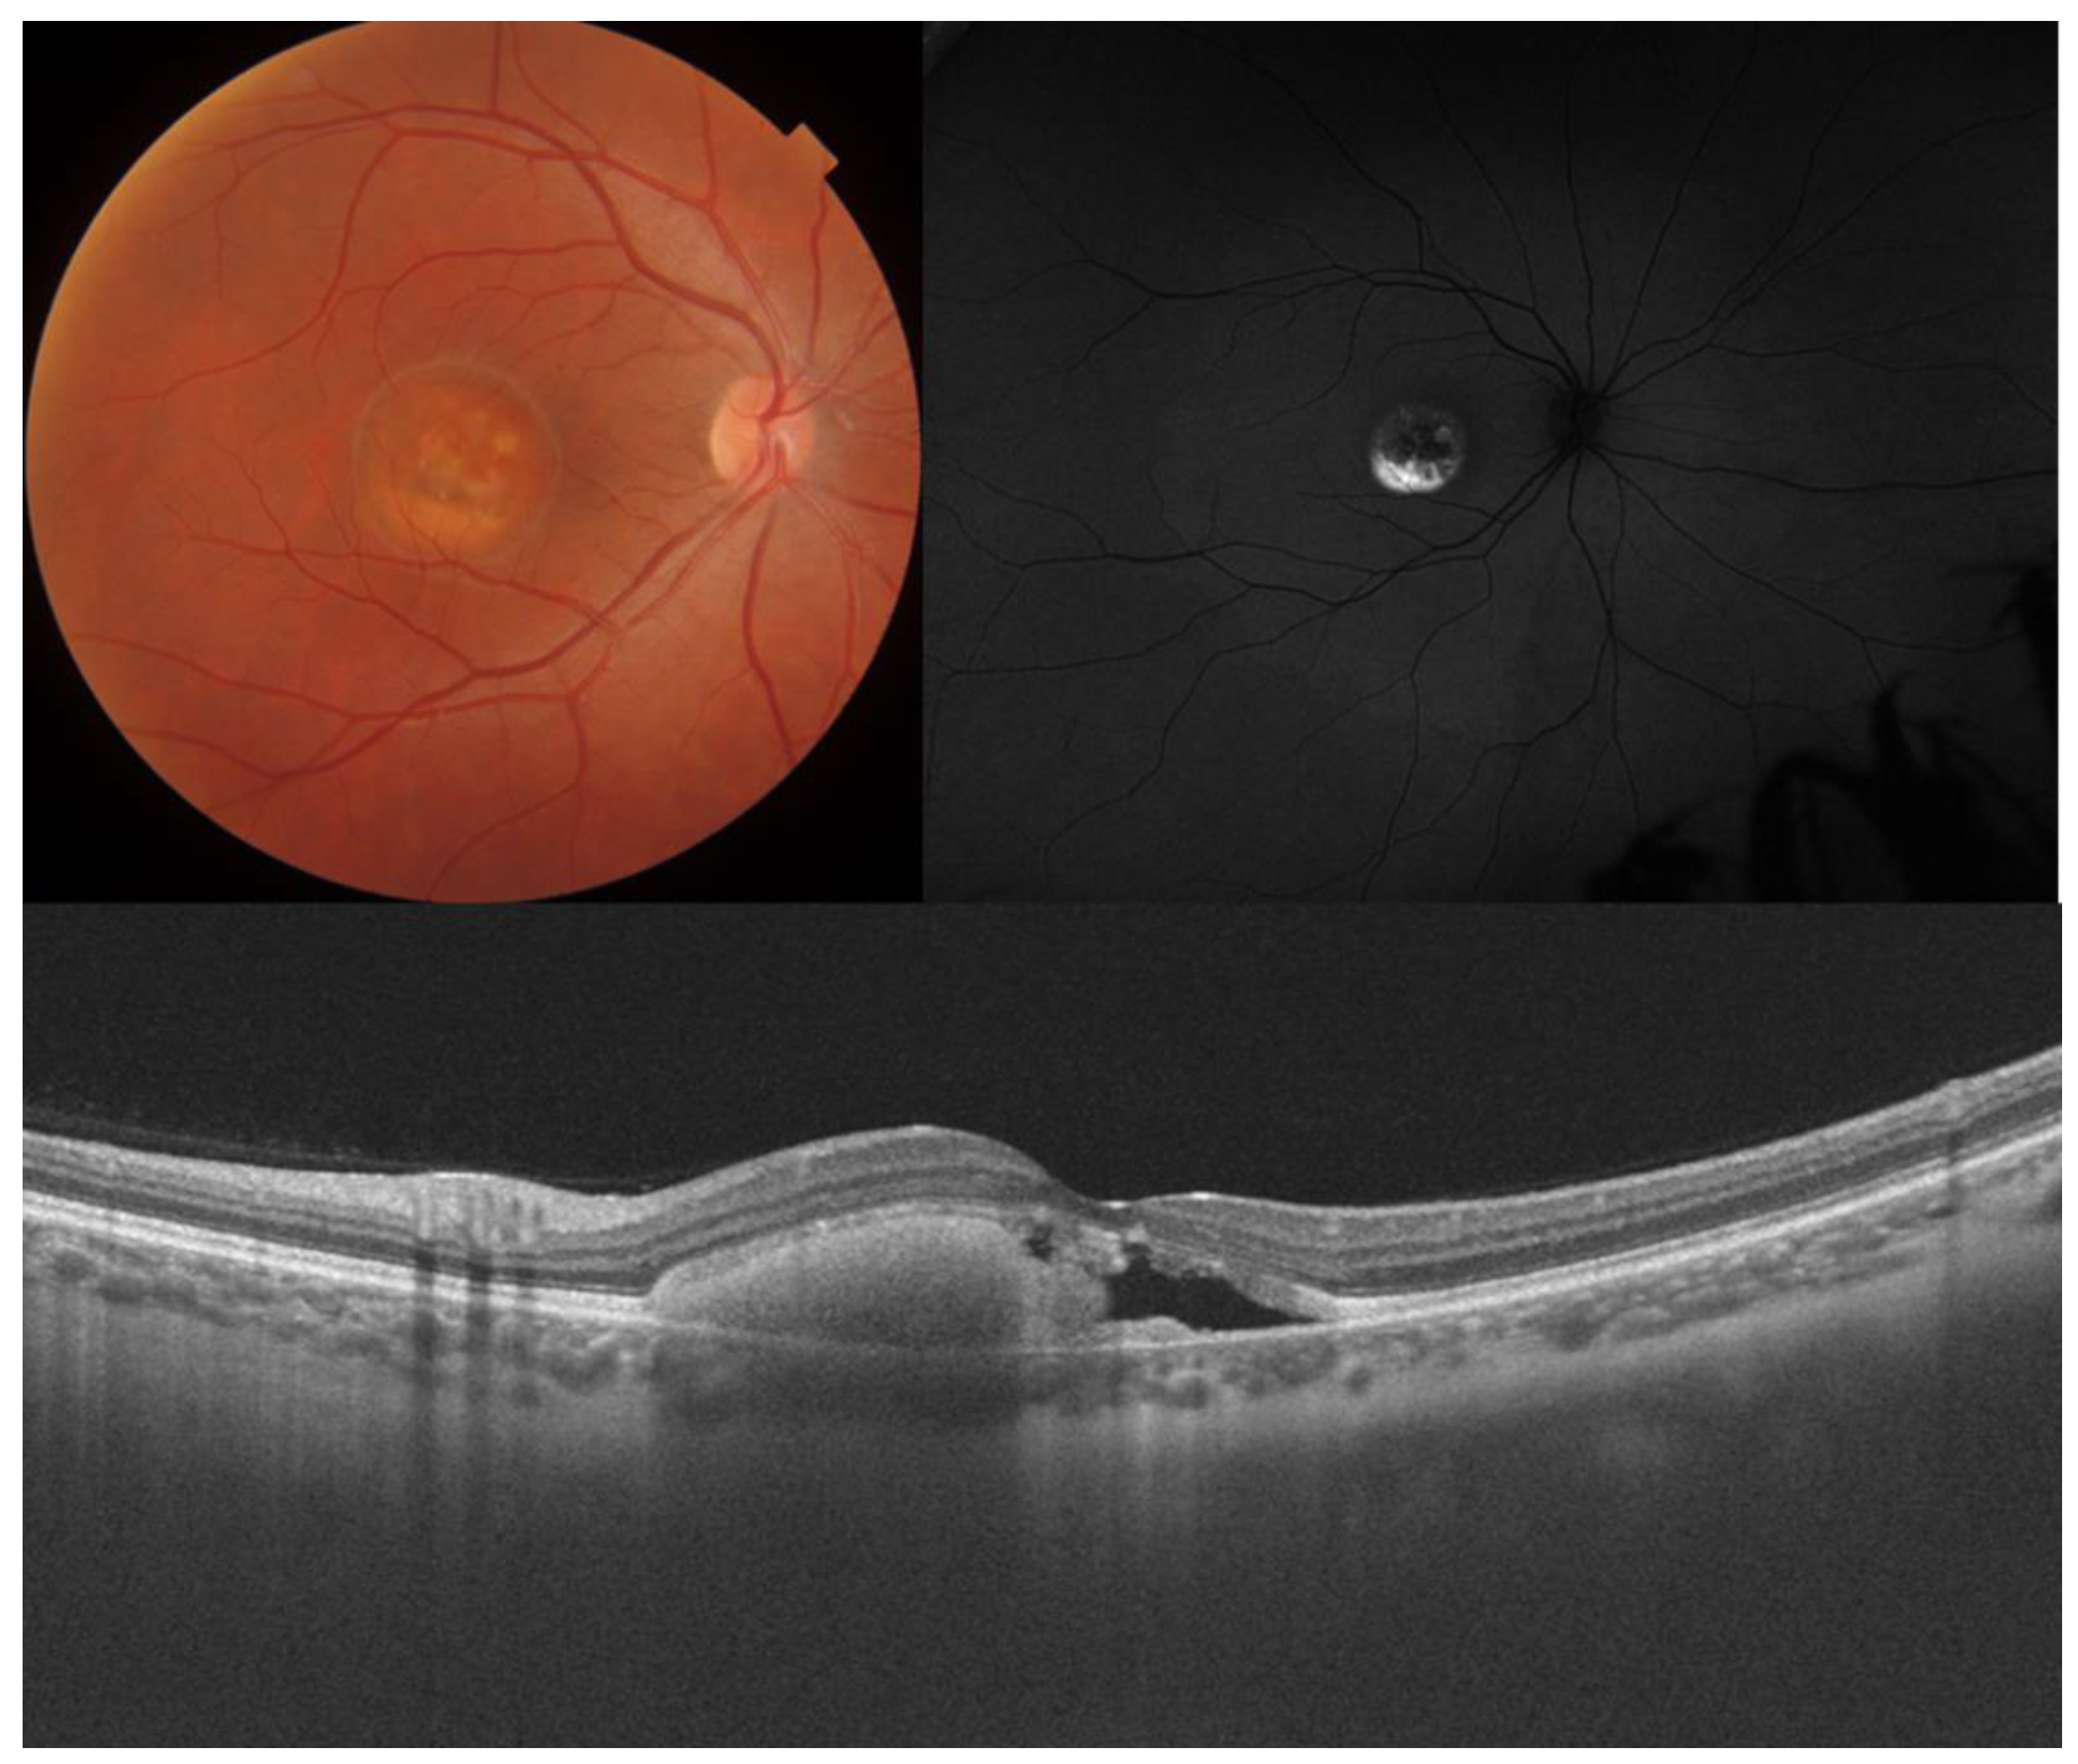

| Best vitelliform macular dystrophy |